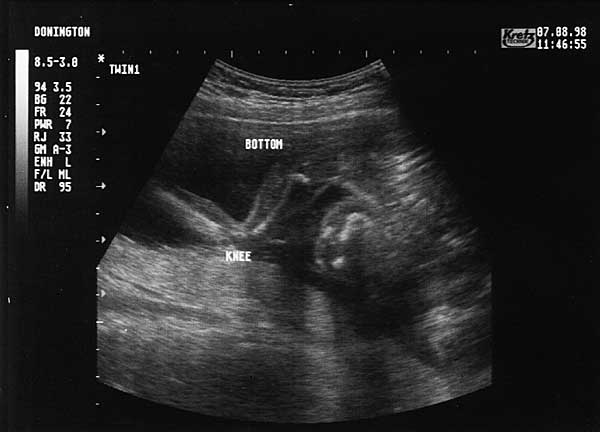

19 Weeks - Friday 7th August 1998.

Nineteen Week Scan 1